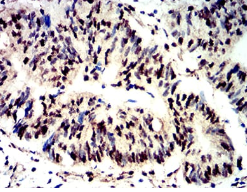

Phospho-4E-BP1 (Ser65) Mouse Monoclonal antibody[2D1G1]

AC3165 Phospho-4E-BP1 (Ser65) Mouse Monoclonal antibody[2D1G1] 100ug $367 10days

Immunogen:    Synthesized peptide of human Phospho-4E-BP1 (Ser65).

IHC    1/200 - 1/1000